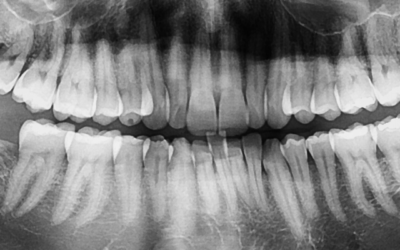

Your dentist will perform a full-mouth examination, checking teeth, gums, jaw, and bite — looking out for early signs of any issues.